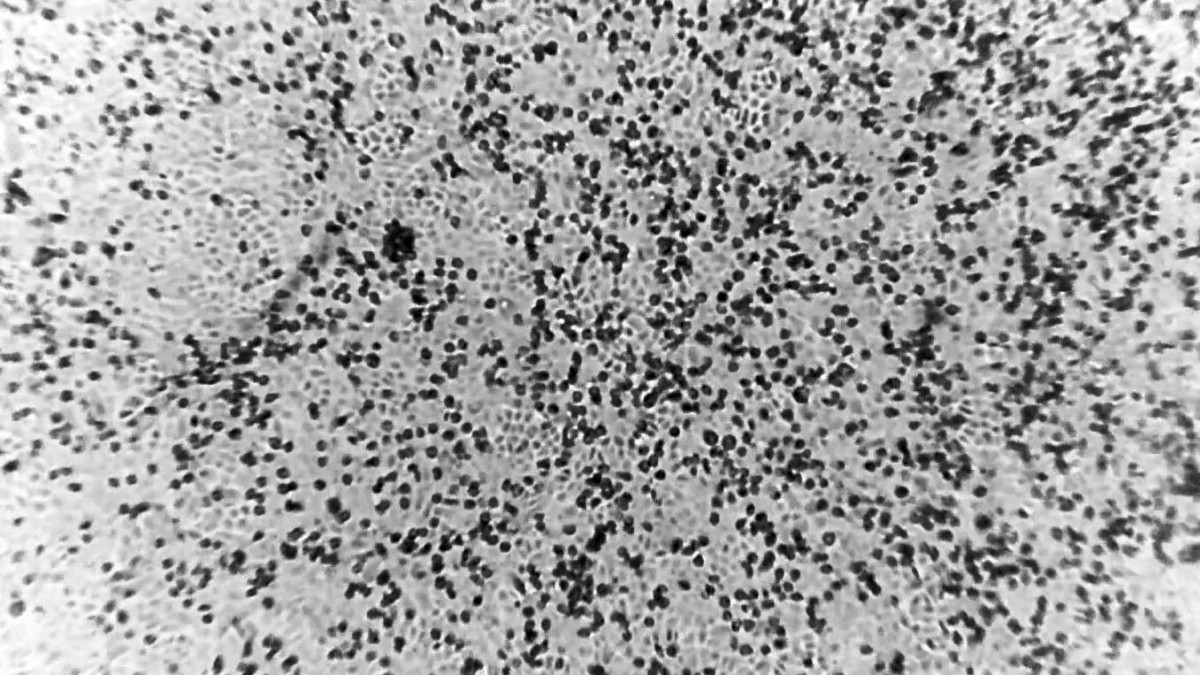

Aterrador: así se esparce por el cuerpo el mortal coronavirus

SÍDNEY – Científicos australianos anunciaron este miércoles que han logrado, por primera vez fuera de China, reproducir el virus de la llamada neumonía de Wuhan, lo que supone un “avance significativo” para encontrar una vacuna. Los investigadores del Centro Peter Doherty, en Melbourne, partieron de la muestra de un paciente infectado para recrear el virus,…